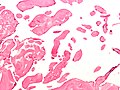

Microscopic

Features:[6]

- Braching papillary fronds which are:

- Composed of collagen, and

- Avascular.

- +/-Elastic tissue.

- Surrounded by:

- Endothelium, and

- Mucopolysaccharide.

Images